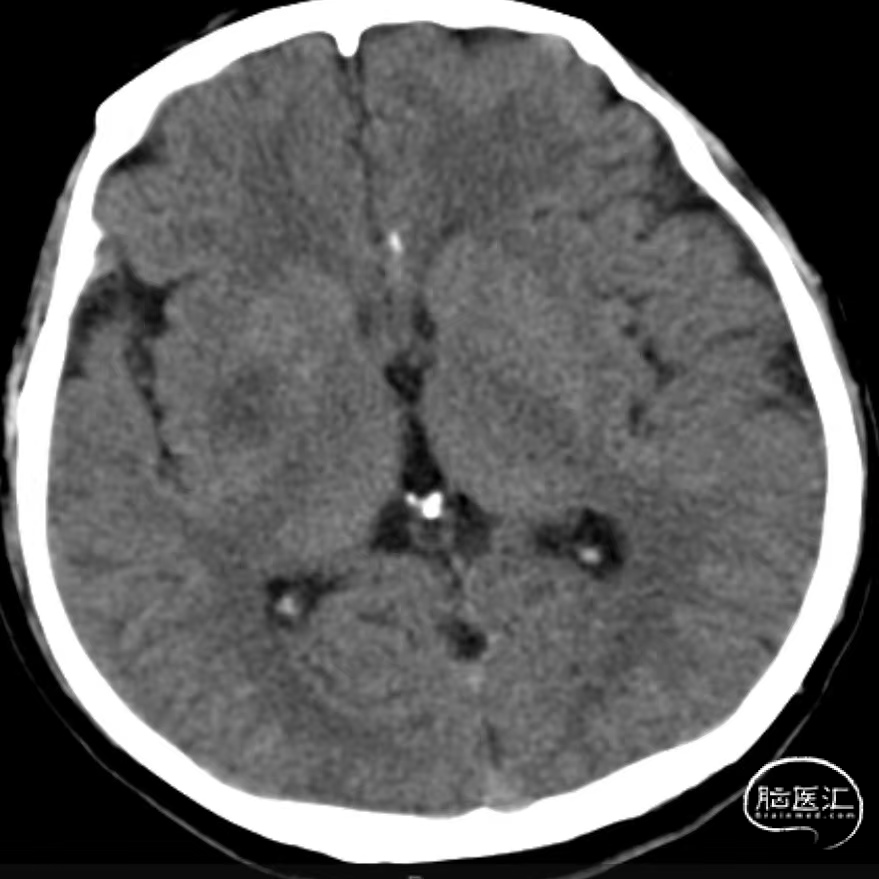

入院时CT:ASPECTS 9分(L1)。

术后即刻复查CT,未见出血及造影剂渗出。